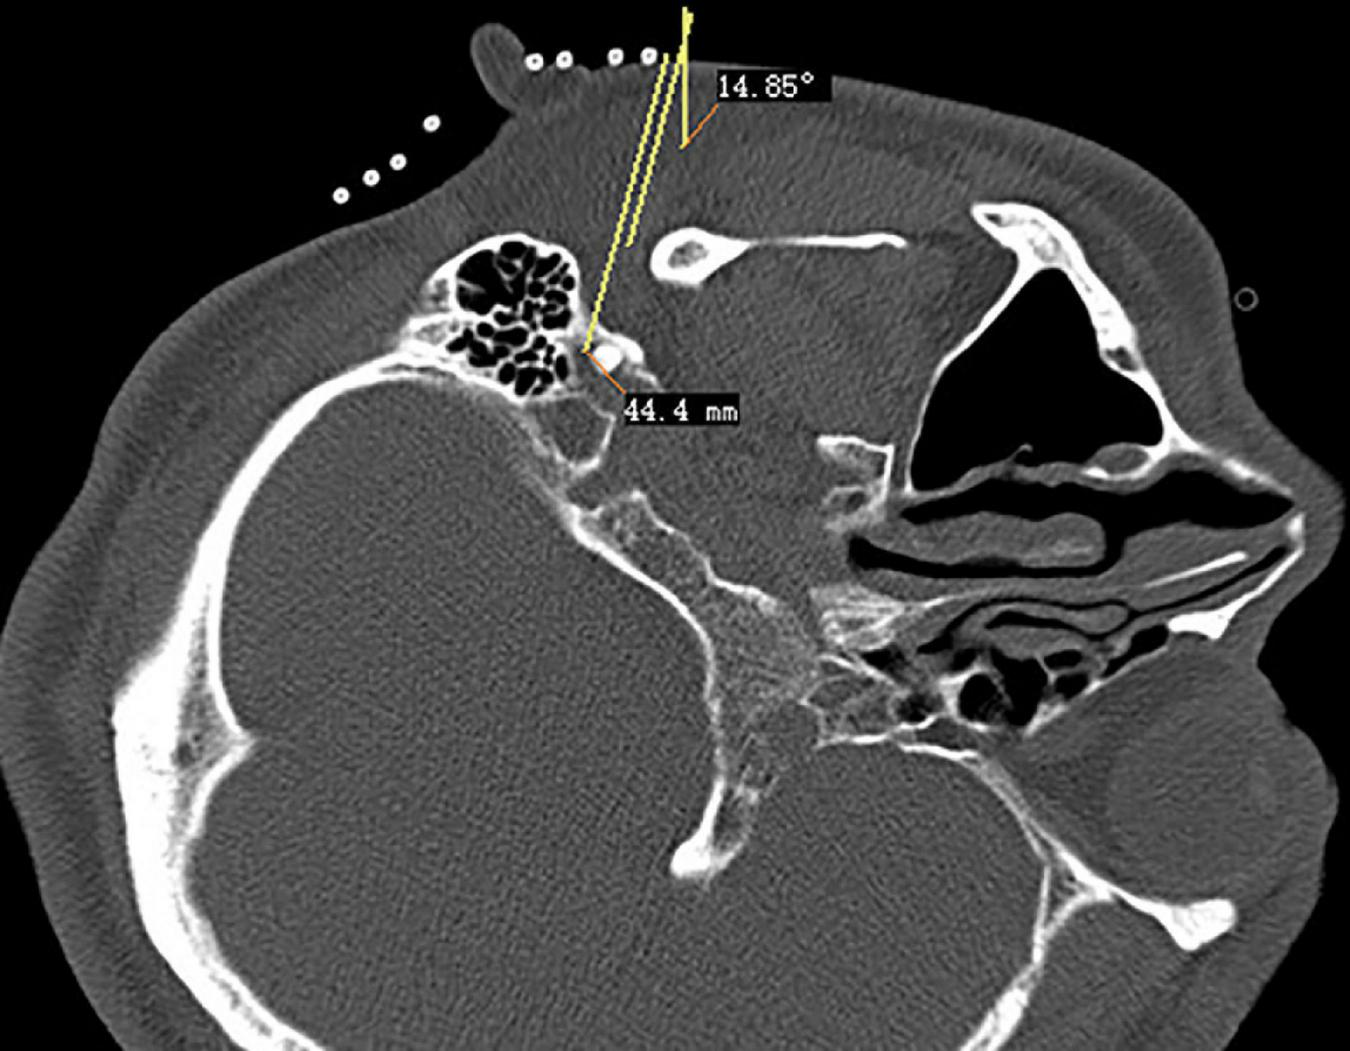

The CT layer with the stylomastoid foramen and without the bone barrier of the tympanic part of the temporal bone was selected as the puncture layer, and the CT measurement tool software was used to pull a straight line forward from the stylomastoid foramen. The intersection of the line and the skin is the puncture point (Figure 2). We determined the puncture depth (the distance from the puncture point to the target) and puncture angle (the angle between the puncture route and sagittal plane). After administering local anesthesia to the puncture site, a stylet 7-gauge radiofrequency needle with a length of 10 cm and an exposed end of 5 mm (Model 240100; Innomed Medical Technology Co., Ltd.) was gradually advanced toward the target under the guidance of intermittent CT inspection (Figure 3) and confirmed by three-dimensional reconstruction of CT scanning (Figure 4). The facial nerve was then stimulated with a radiofrequency probe at a frequency of 2 Hz and a current capacity of 0.5 mA (RF instrument model PMG230; Baylis Medical Co., Inc.). The positive facial muscle twitches from the stimulation indicated that the facial nerve was in close proximity (Supplementary Video 1).

FIGURE 2

Puncture path design of stylomastoid foramen.